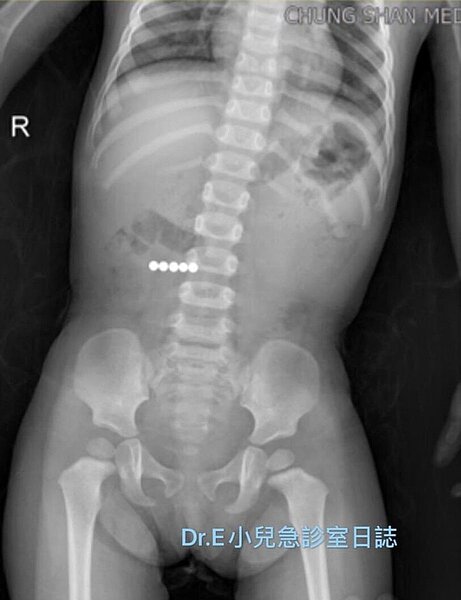

一歲男童將家裡的巴克球吞到肚子裡, X光下可以看到五個閃亮的白點。圖/取自臉書

謝宗學在臉書上分享這個案例,1歲多的男童因為前一天滑倒撞到頭部後開始噁心嘔吐,到急診室後經過醫師診視安排頭部電腦斷層掃描,並沒有發現異常。因為持續嘔吐,考慮腸胃道疾病,安排了腹部X光,意外發現有5顆相連在一起的「白亮球形異物」在腸道中。